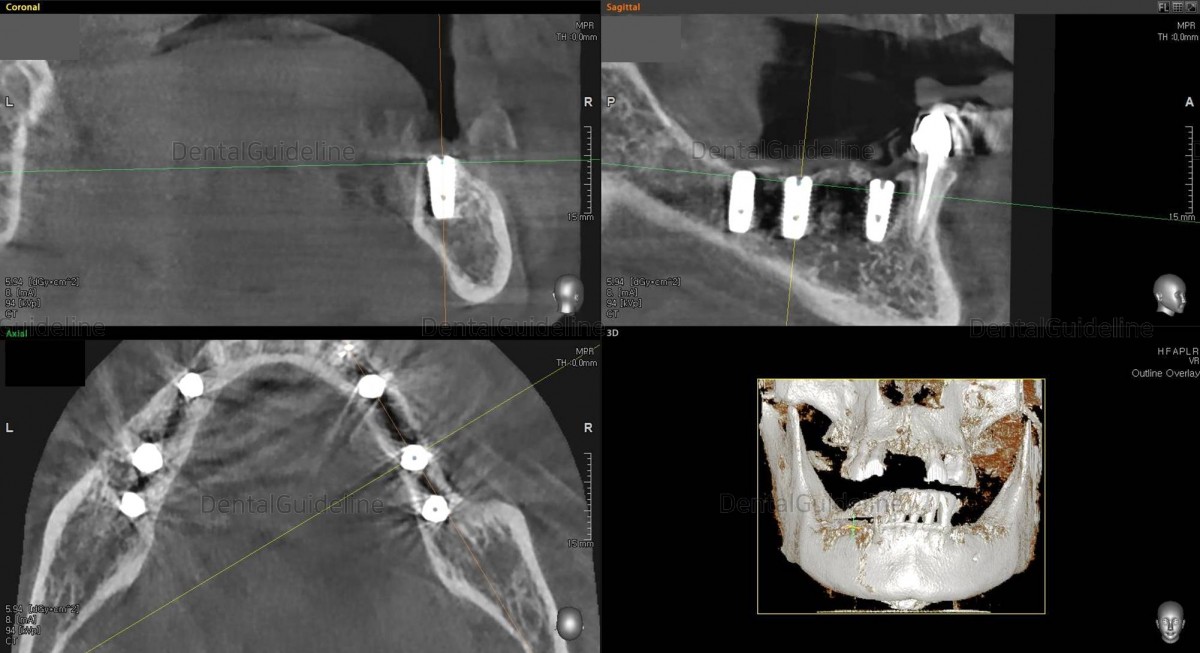

CBCT scan Arum NB-1 Ø4.5./ L10

(20Ncm) at

the 1st molar zone.

CBCT scan Arum NB-1 Ø4.5/ L10

the 2nd molar zone.Arm Dentistry NB-1 Ø4.5/ L10